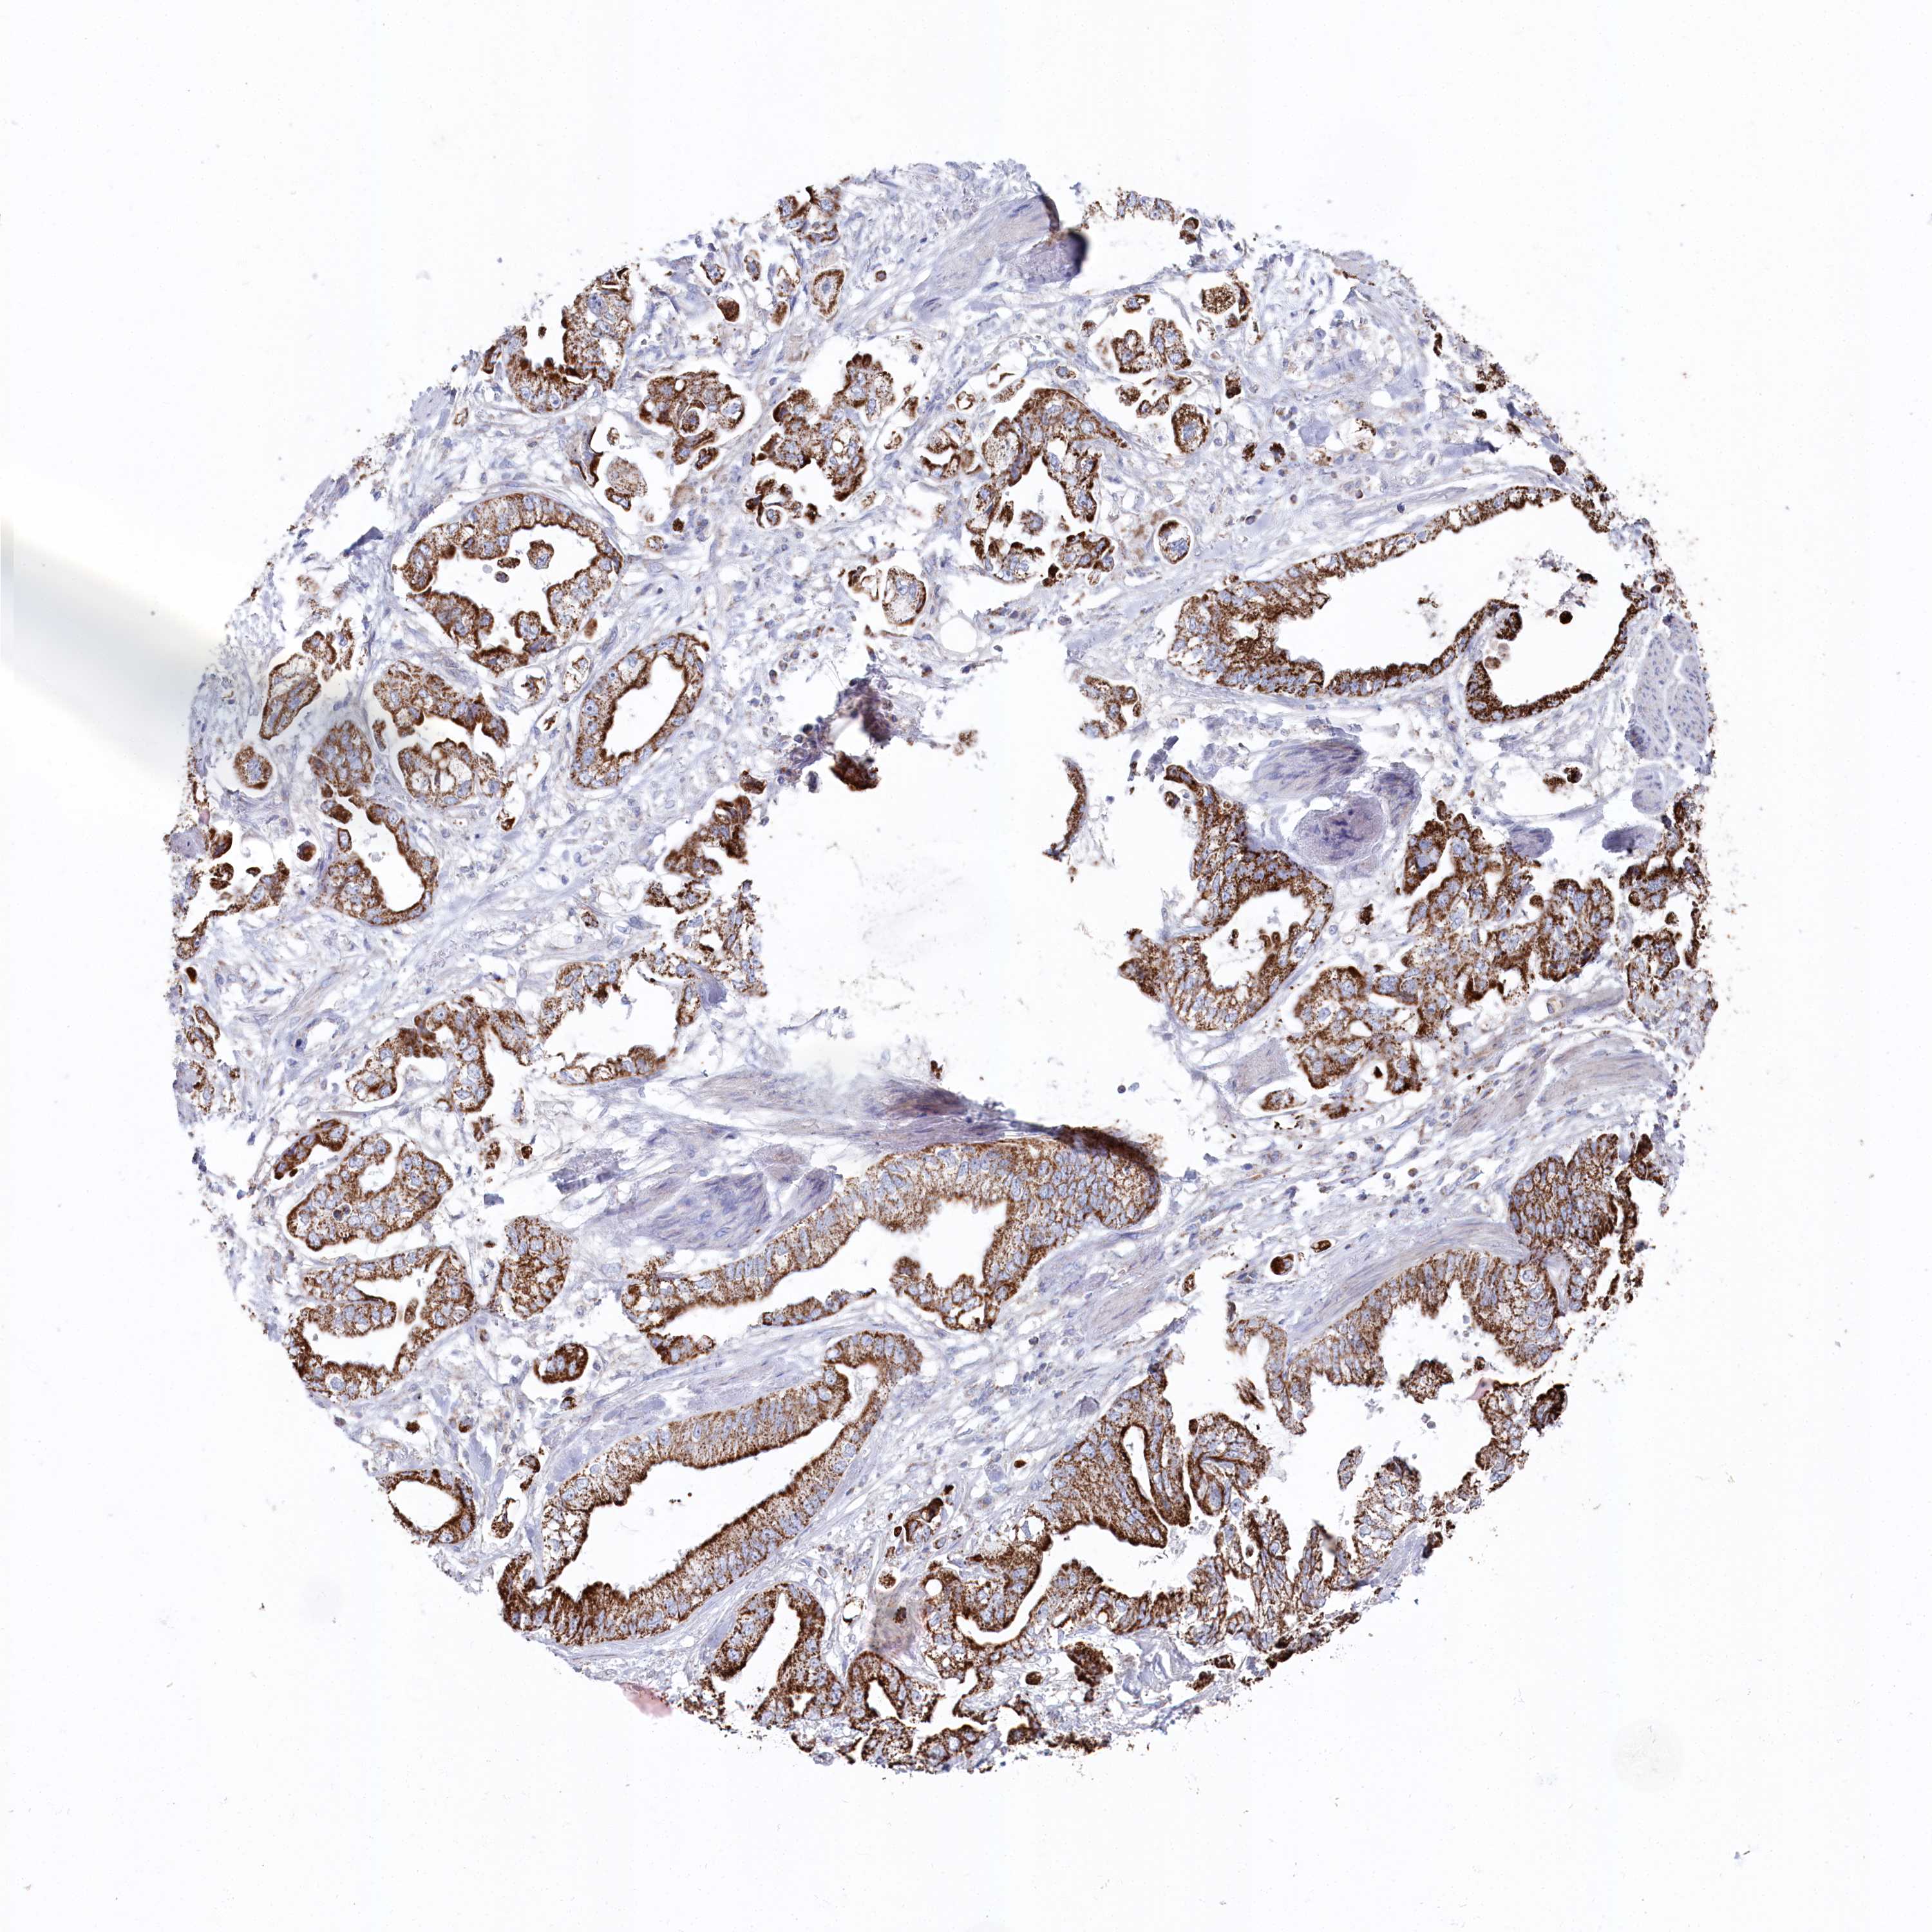

STOMACH CANCER - Protein expressioni

A mouse-over function shows sample information and annotation data. Click on an image to view it in a full screen mode. Samples can be filtered based on level of antibody staining by selecting one or several of the following categories: high, medium, low and not detected. The assay and annotation is described here.

Note that samples used for immunohistochemistry by the Human Protein Atlas do not correspond to samples in the TCGA dataset.

Antibody stainingi

Antibody staining in the annotated cell types in the current human tissue is reported as not detected, low, medium, or high, based on conventional immunohistochemistry profiling in selected tissues. This score is based on the combination of the staining intensity and fraction of stained cells.

Each image is clickable and will lead to virtual microscopy that enables deeper exploration of all samples and also displays staining intensity scores, fraction scores and subcellular localization as well as patient and tissue information for each sample.

Antibody HPA038608

Staining

High

Medium

Low

Not detected

Intensity

Strong

Moderate

Weak

Negative

Quantity

>75%

75%-25%

<25%

None

Location

Nuclear

Cytoplasmic/membranous

Cytoplasmic/membranous,nuclear

Adenocarcinoma, NOS

Adenocarcinoma, High grade